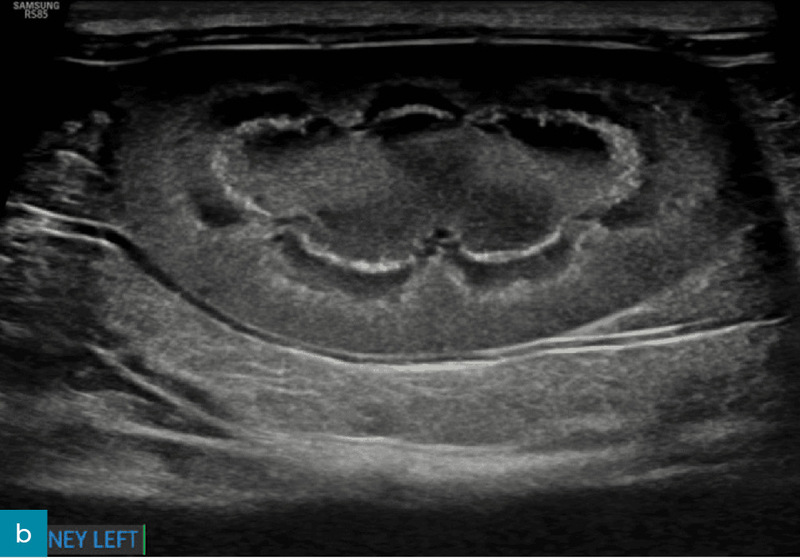

Torbiele nerek

Torbiele nerek (ryc. 12) występują częściej w korze nerkowej i mogą mieć charakter nabyty lub wrodzony. Dlatego też nie stanowią one czułego wskaźnika przewlekłej choroby nerek u psów, jeżeli nie mamy do porównania wcześniej wykonanego badania.8,17 Torbiele nerek są często stwierdzane u psów z przewlekłą chorobą nerek i zazwyczaj nie wpływają istotnie na czynność narządu. Mogą jednak zmieniać kształt nerek i być jednym z czynników powodujących nieregularność ich brzegów.8,12,21

Ryc. 12. Obraz w projekcji strzałkowej (a) i poprzecznej (b) lewej nerki psa, uzyskany odpowiednio za pomocą głowicy mikrokonweksowej i liniowej. W centrum kory nerkowej widoczna jest dobrze odgraniczona, gładko obramowana, cienkościenna, okrągła, bezechowa torbiel ze wzmocnieniem dalszym. Kora nerkowa wykazuje słabo zdefiniowane hiperechogeniczne prążkowanie oraz zmniejszone zróżnicowanie korowo-rdzeniowe. Łagodna pielektazja (wysokość miedniczki nerkowej < 2 mm) była głównie uznawana za wtórną do diurezy (na przykład fizjologicznej, spowodowanej dożylnym podaniem płynów bądź niewydolnością nerek). Obraz w projekcji strzałkowej dodatkowo wykazuje poprawę rozdzielczości przestrzennej przy użyciu głowic liniowych o wyższej częstotliwości.